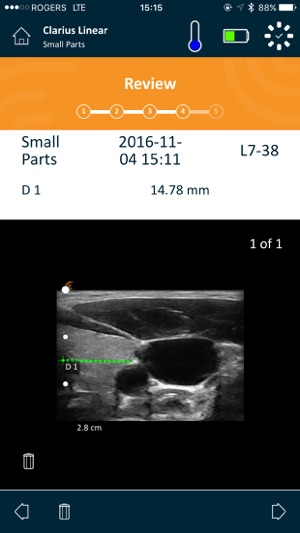

Clarius is the only Handheld Wireless Ultrasound Scanner that doesn’t compromise on image quality. Designed as a Point-and-Shoot Ultrasound™ system, it has automated and optimized gain and frequency settings to capture images quickly. Or you can easily use manual settings to adjust images to your liking.

Our multipurpose Clarius C3 ultrasound scanner is designed to image the abdomen and lungs; it also works as a virtual phased array for quick scans of the heart. The Clarius L7 linear scanner is ideal for guiding procedures such as nerve blocks and targeted injections. For more information about Clarius Scanners, please visit www.clarius.com.